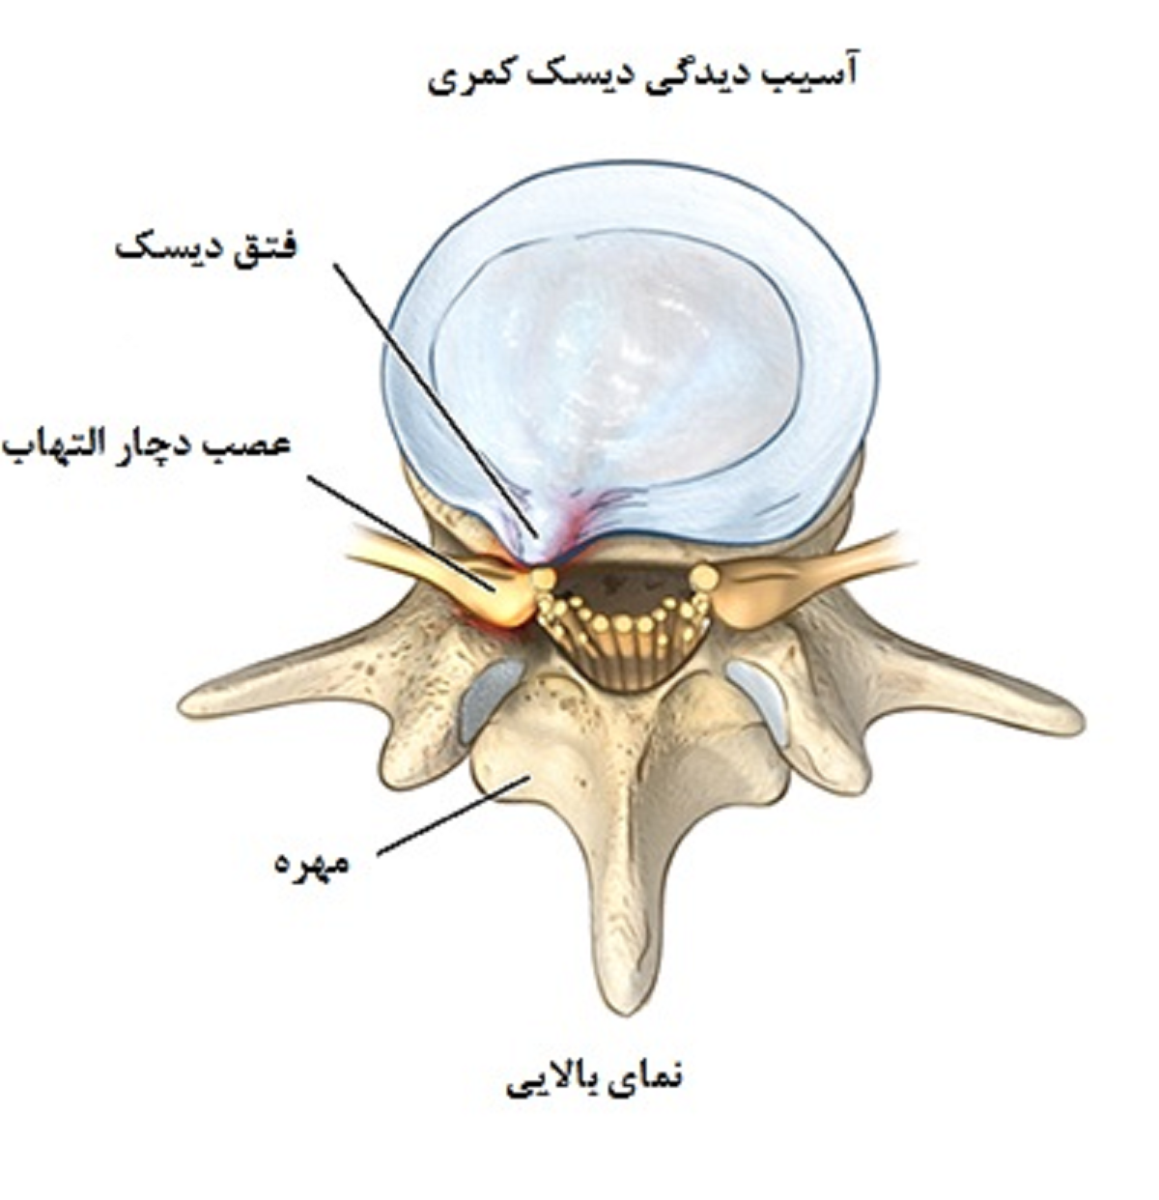

بیرون زدگی دیسک یا فتق دیسک کمر

دررفتگی یا بیرون زدگی دیسک کمر به عنوان یک اختلال دیسک از نوع contained نیز شناخته میشود. این بدان معنی است که مرکز ژل مانند (نوکلئوس پالپوزوس) در داخل دیواره بیرونی مانند لاستیک مانند دیسک خود (آنولوس فیبروز) دیسک “موجود” (contained) باقی میماند.فتق دیسک هنگامی رخ میدهد که نوکلئوس یا هسته از فیبروز آنولوس یا حلقهی فیبری بیرون بزند. به این بیماری اختلال دیسک ” non-contained” گفته میشود. چه دیسک دچار برآمدگی یا دچار فتق شود ، مواد دیسک میتوانند روی ریشه عصب مجاور فشار وارد کنند و بافت عصبی ظریف را فشرده کرده و باعث ایجاد فشردگی و درد سیاتیک شوند.

عواقب ناشی از فتق دیسک بدتر هستند. فتق دیسک نه تنها باعث فشار مستقیم ریشه عصب روی قسمت داخلی کانال نخاع استخوانی میشود، بلکه خود مادهی دیسک نیز حاوی یک ماده محرک اسیدی، شیمیایی (اسید هیالورونیک) است که باعث التهاب عصب میشود. در هر دو حالت، فشردگی و تحریک عصب باعث التهاب و درد شده که غالباً منجر به بیحسی اندام، احساس سوزن سوزن شدن و یا ضعف عضلات میشود.